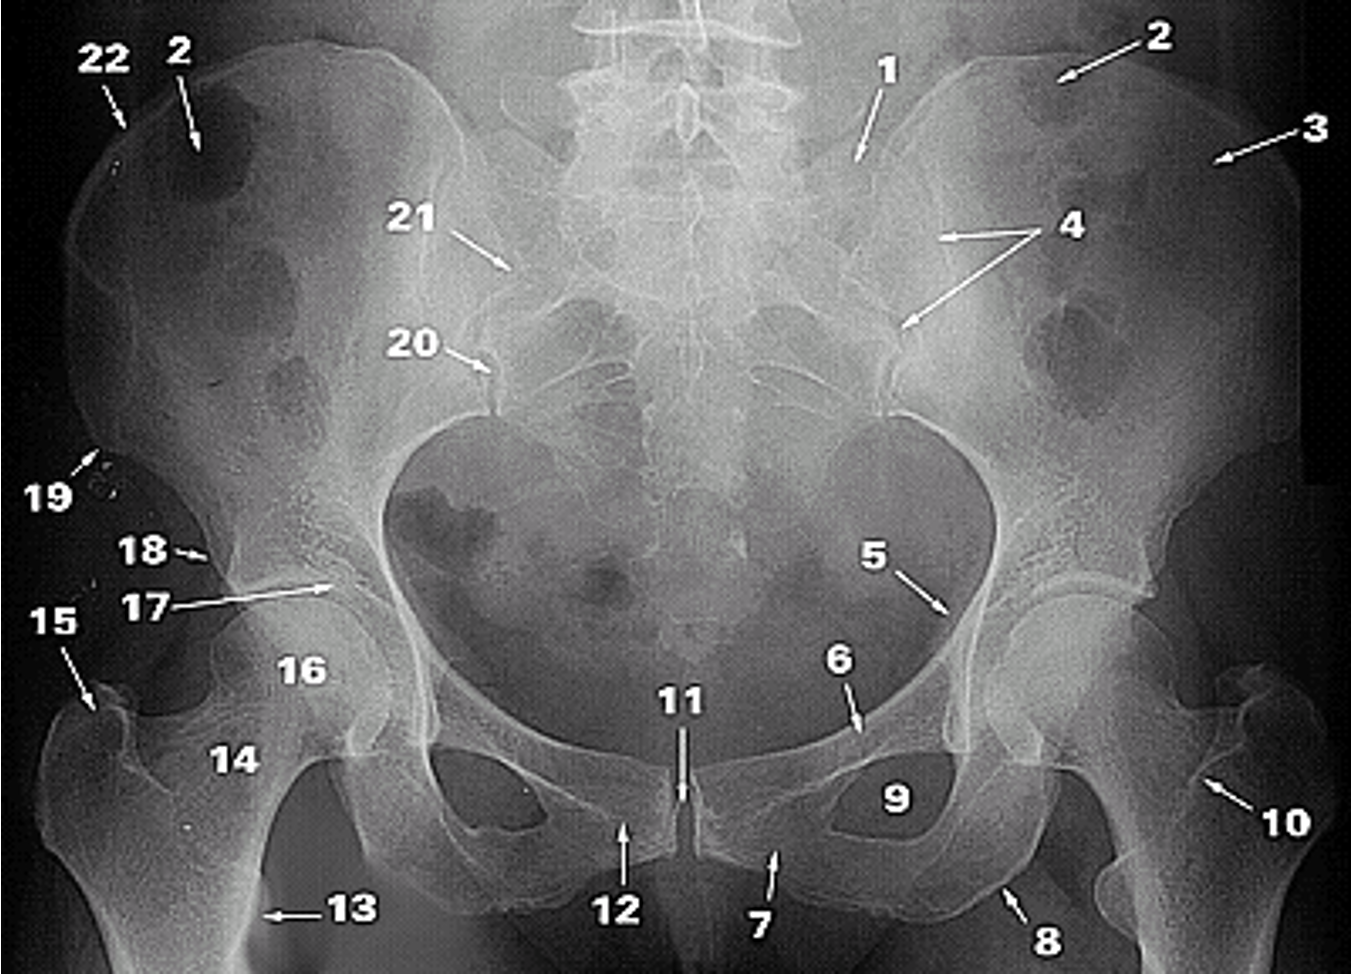

<p>1.</p>

Lateral Part of the Sacrum

<p>2.</p>

Gas in colon

<p>3.</p>

Ilium

<p>4.</p>

Sacroiliac Joint

<p>5.</p>

Ischial Spine

<p>6.</p>

Superior Ramus of Pubis

<p>7.</p>

Inferior Ramus of Pubis

<p>8.</p>

Ischial Tuberosity

<p>9.</p>

Obturator Foramen

<p>10.</p>

Intertrochanteric Crest

<p>11.</p>

Pubic Symphysis

<p>12.</p>

Pubic Tubercle

<p>13.</p>

Lesser Trochanter

<p>14.</p>

Neck of Femur

<p>15.</p>

Greater Trochanter

<p>16.</p>

Head of Femur

<p>17.</p>

Acetabular Fossa

<p>18.</p>

Anterior Inferior Iliac Spine

<p>19.</p>

Anterior Superior Iliac Spine

<p>20.</p>

Posterior Inferior Iliac Spine

<p>21.</p>

Posterior Superior Iliac Spine

<p>22.</p>

Iliac Crest